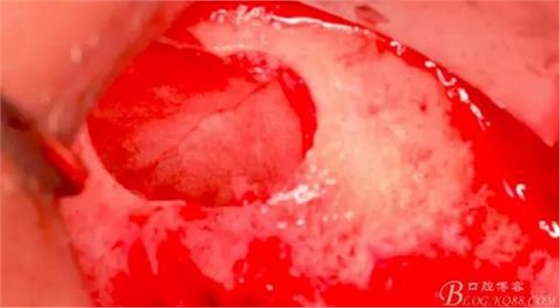

水壓將頰側(cè)上頜竇膜剝離。

擴(kuò)大窗口,此時(shí)因?yàn)樯项M竇膜已經(jīng)與骨壁分離,所以打磨時(shí)不會(huì)損傷到膜。